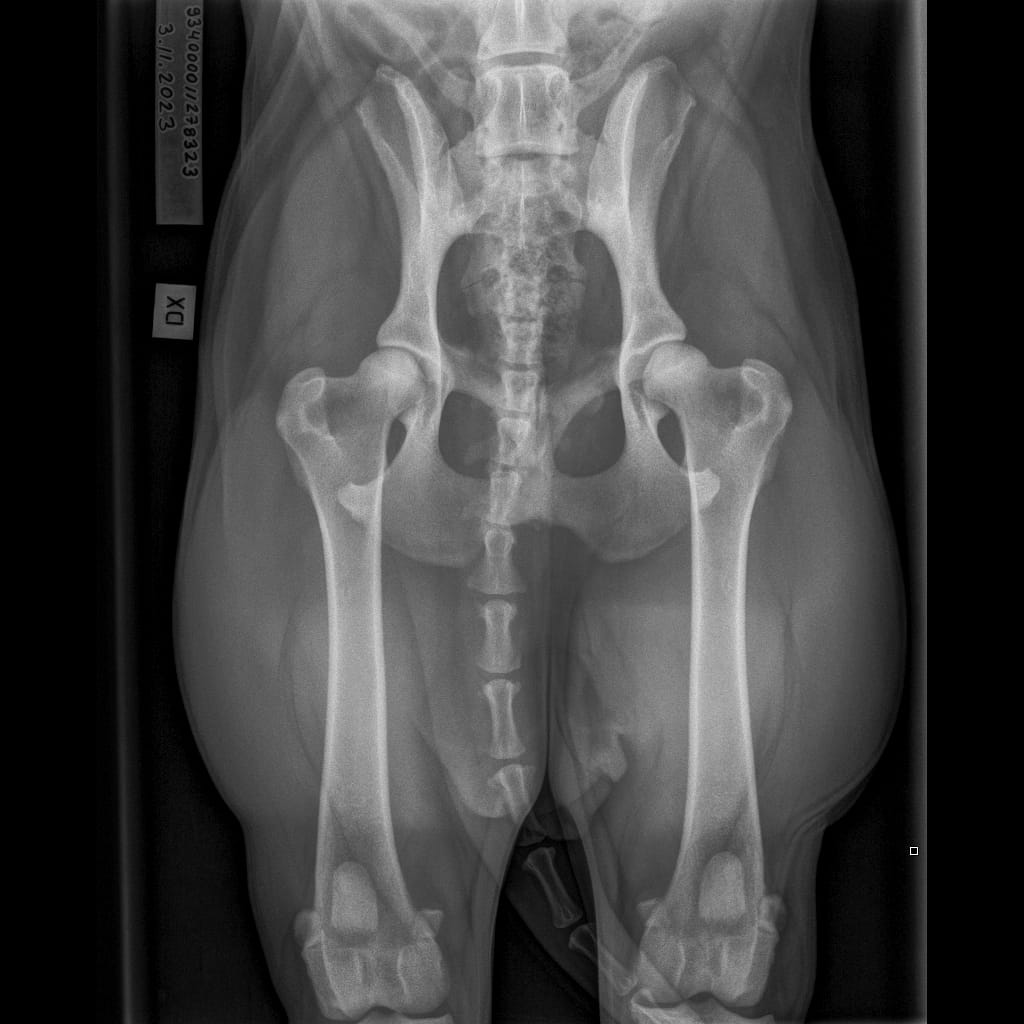

Lumbosacral transitional vertebra (LTV) in Rhodesian Ridgebacks